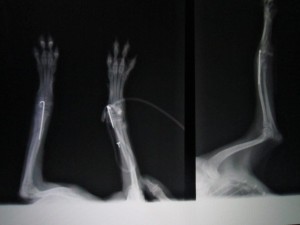

術後のレントゲンです。

今回はピンで整復しました。